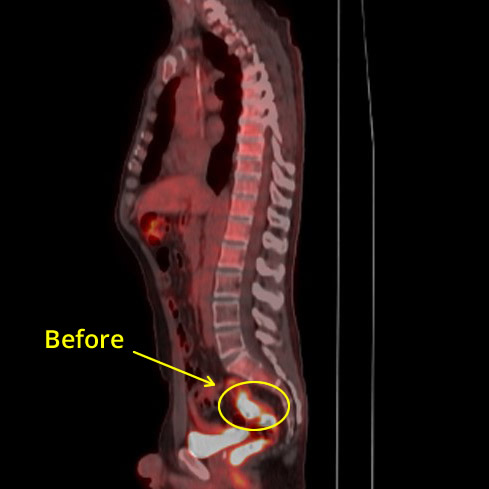

Colon CXR Before

Colon CXR After